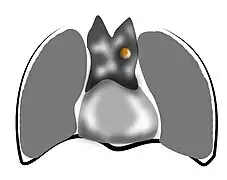

- Aspect scannographique

Présentation tomodensitométrique classique d'un thymome à un stade précoce (cercle rouge). À l'arrière, l'aorte, la veine cave supérieure et l'artère pulmonaire sont visibles en coupe.

Présentation tomodensitométrique classique d'un thymome à un stade précoce (cercle rouge). À l'arrière, l'aorte, la veine cave supérieure et l'artère pulmonaire sont visibles en coupe. Scanner injecté, en fenêtre médiastinale, montrant un carcinome thymique envahissant les structures médiastinales :